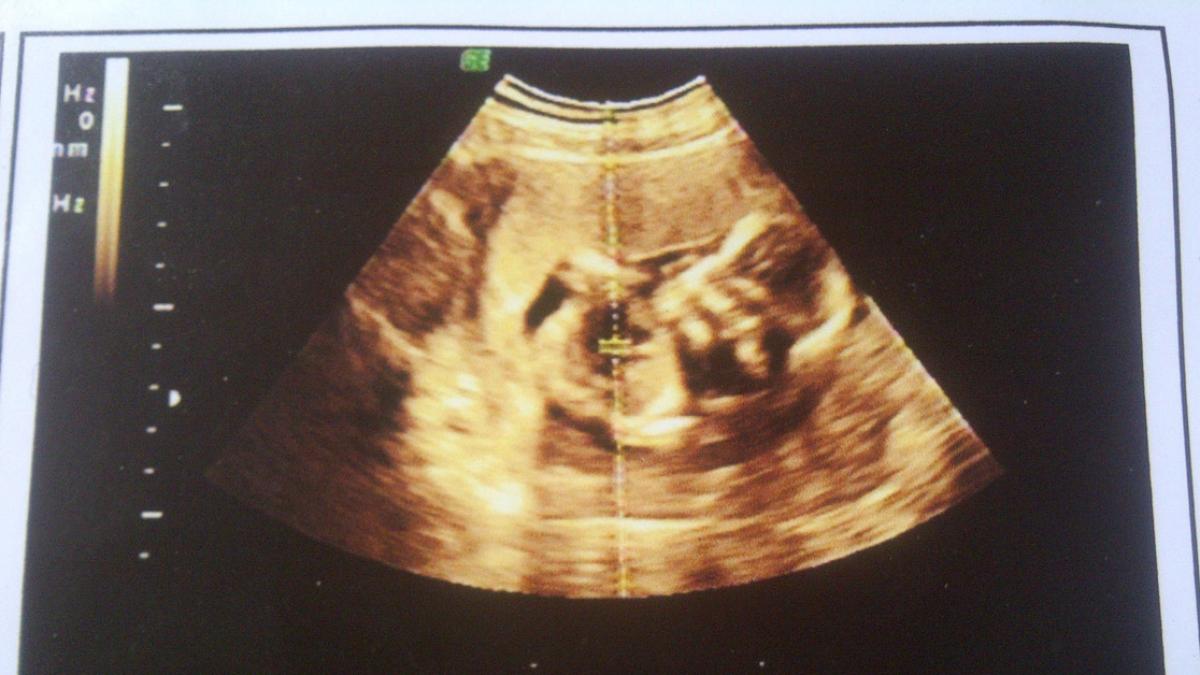

Siêu âm thai giúp chẩn đoán tim thai, sự phát triển của em bé, tính toàn tuổi thai và ngày dự sinh…